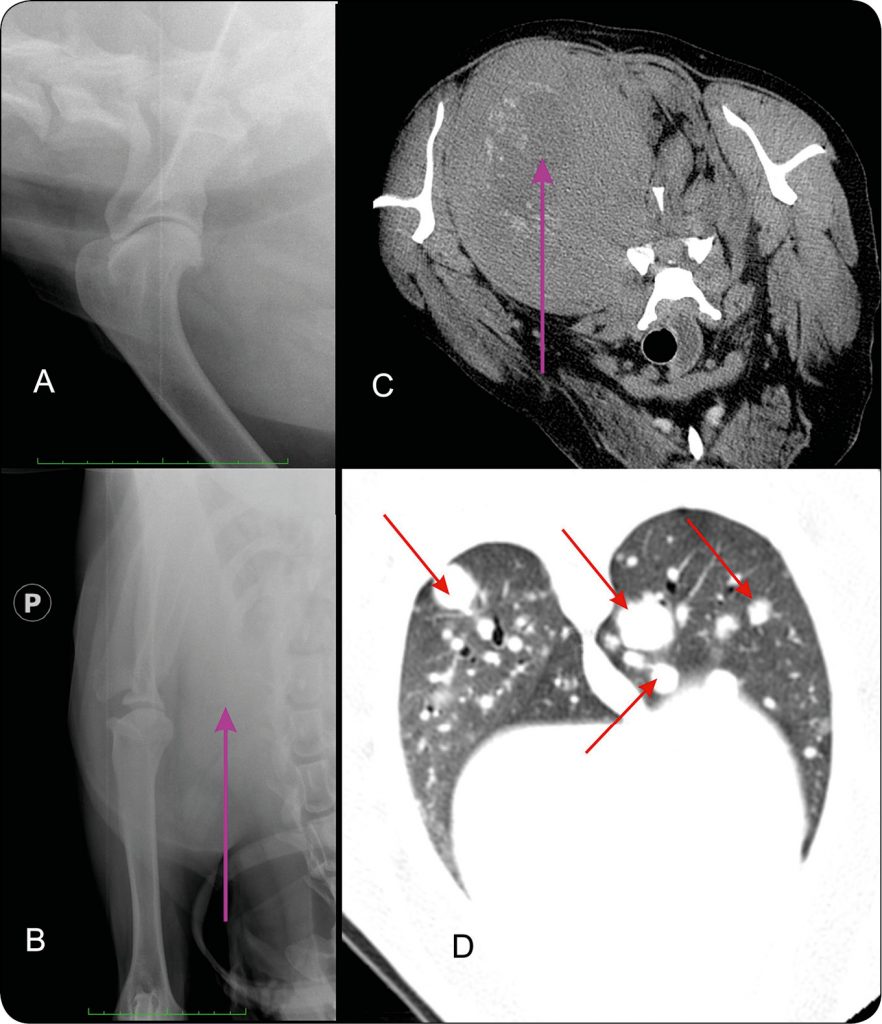

Na badanie RTG stawu ramiennego i łopatki lewej do Pracowni Diagnostyki Obrazowej Kliniki został skierowany pies, samiec, rasy pirenejski pies górski, w wieku 9 lat. Powodem skierowania była nasilająca się kulawizna kończyny piersiowej lewej oraz wyczuwalny w badaniu klinicznym guz okolicy łopatkowej. Wykonano badanie RTG doogonowo-boczno-doczaszkowoprzyśrodkowe skośne łopatki oraz doogonowo-doczaszkowe stawu ramiennego lewego (ryc. 9). W obrazie stwierdzono rozległy obszar osteolizy łopatki, dotyczący głównie dołu nadgrzebieniowego i grzebienia. Opisany obszar osteolizy miał niewyraźne granice z kością zdrową, obecne były również niejednorodne obszary osteosklerotyzacji. Wykonano biopsję Tru-Cut zmiany, w wyniku badania histopatologicznego stwierdzono proces o typie mięsaka.